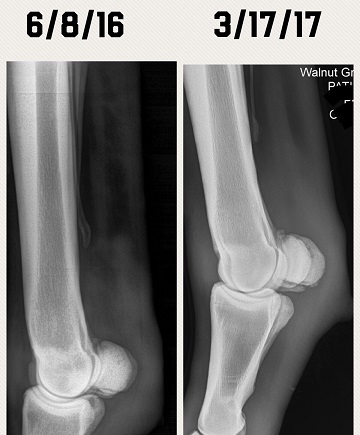

Just wanting to see if anyone had any opinions on these X-rays. Diagnosis was a fractured sesamoid bone. Before and after X-rays in the pics. Do they look any better? Does he have any hope for a barrel future? Anyone experienced this before? Completely sound in the pasture at this time. Has not been put back to work yet. Thanks man advance.

(xray 1.JPG)

(xray 2.JPG)

(xray3.JPG)

(6-1-16 side2.jpg)

Still looks like a chip is floating around in there.

How old is this horse? I do see what looks like a bone chip floating around

The vet has said it has calcified some. He hasn't said anything about a chip in there. I don't know if it is something that will break off or just calcify and heal up in the next few years.